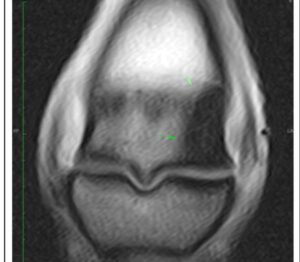

Signs: Bone edema or bone bruising are painful, so your horse will be sore. Your vet can isolate the painful area with nerve blocks, but sophisticated imaging techniques may be necessary to identify the cause. X-rays will not show microscopic bone damage, but a edema/hematoma may appear as a “hot spot” on a nuclear bone scan. MRI is a good diagnostic technology to outline the edema/hematoma.

MRI-Bone Edema